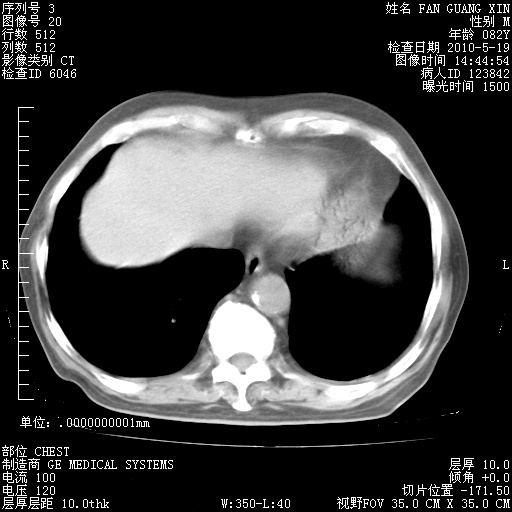

再治疗10天后的肺部CT 纵膈窗